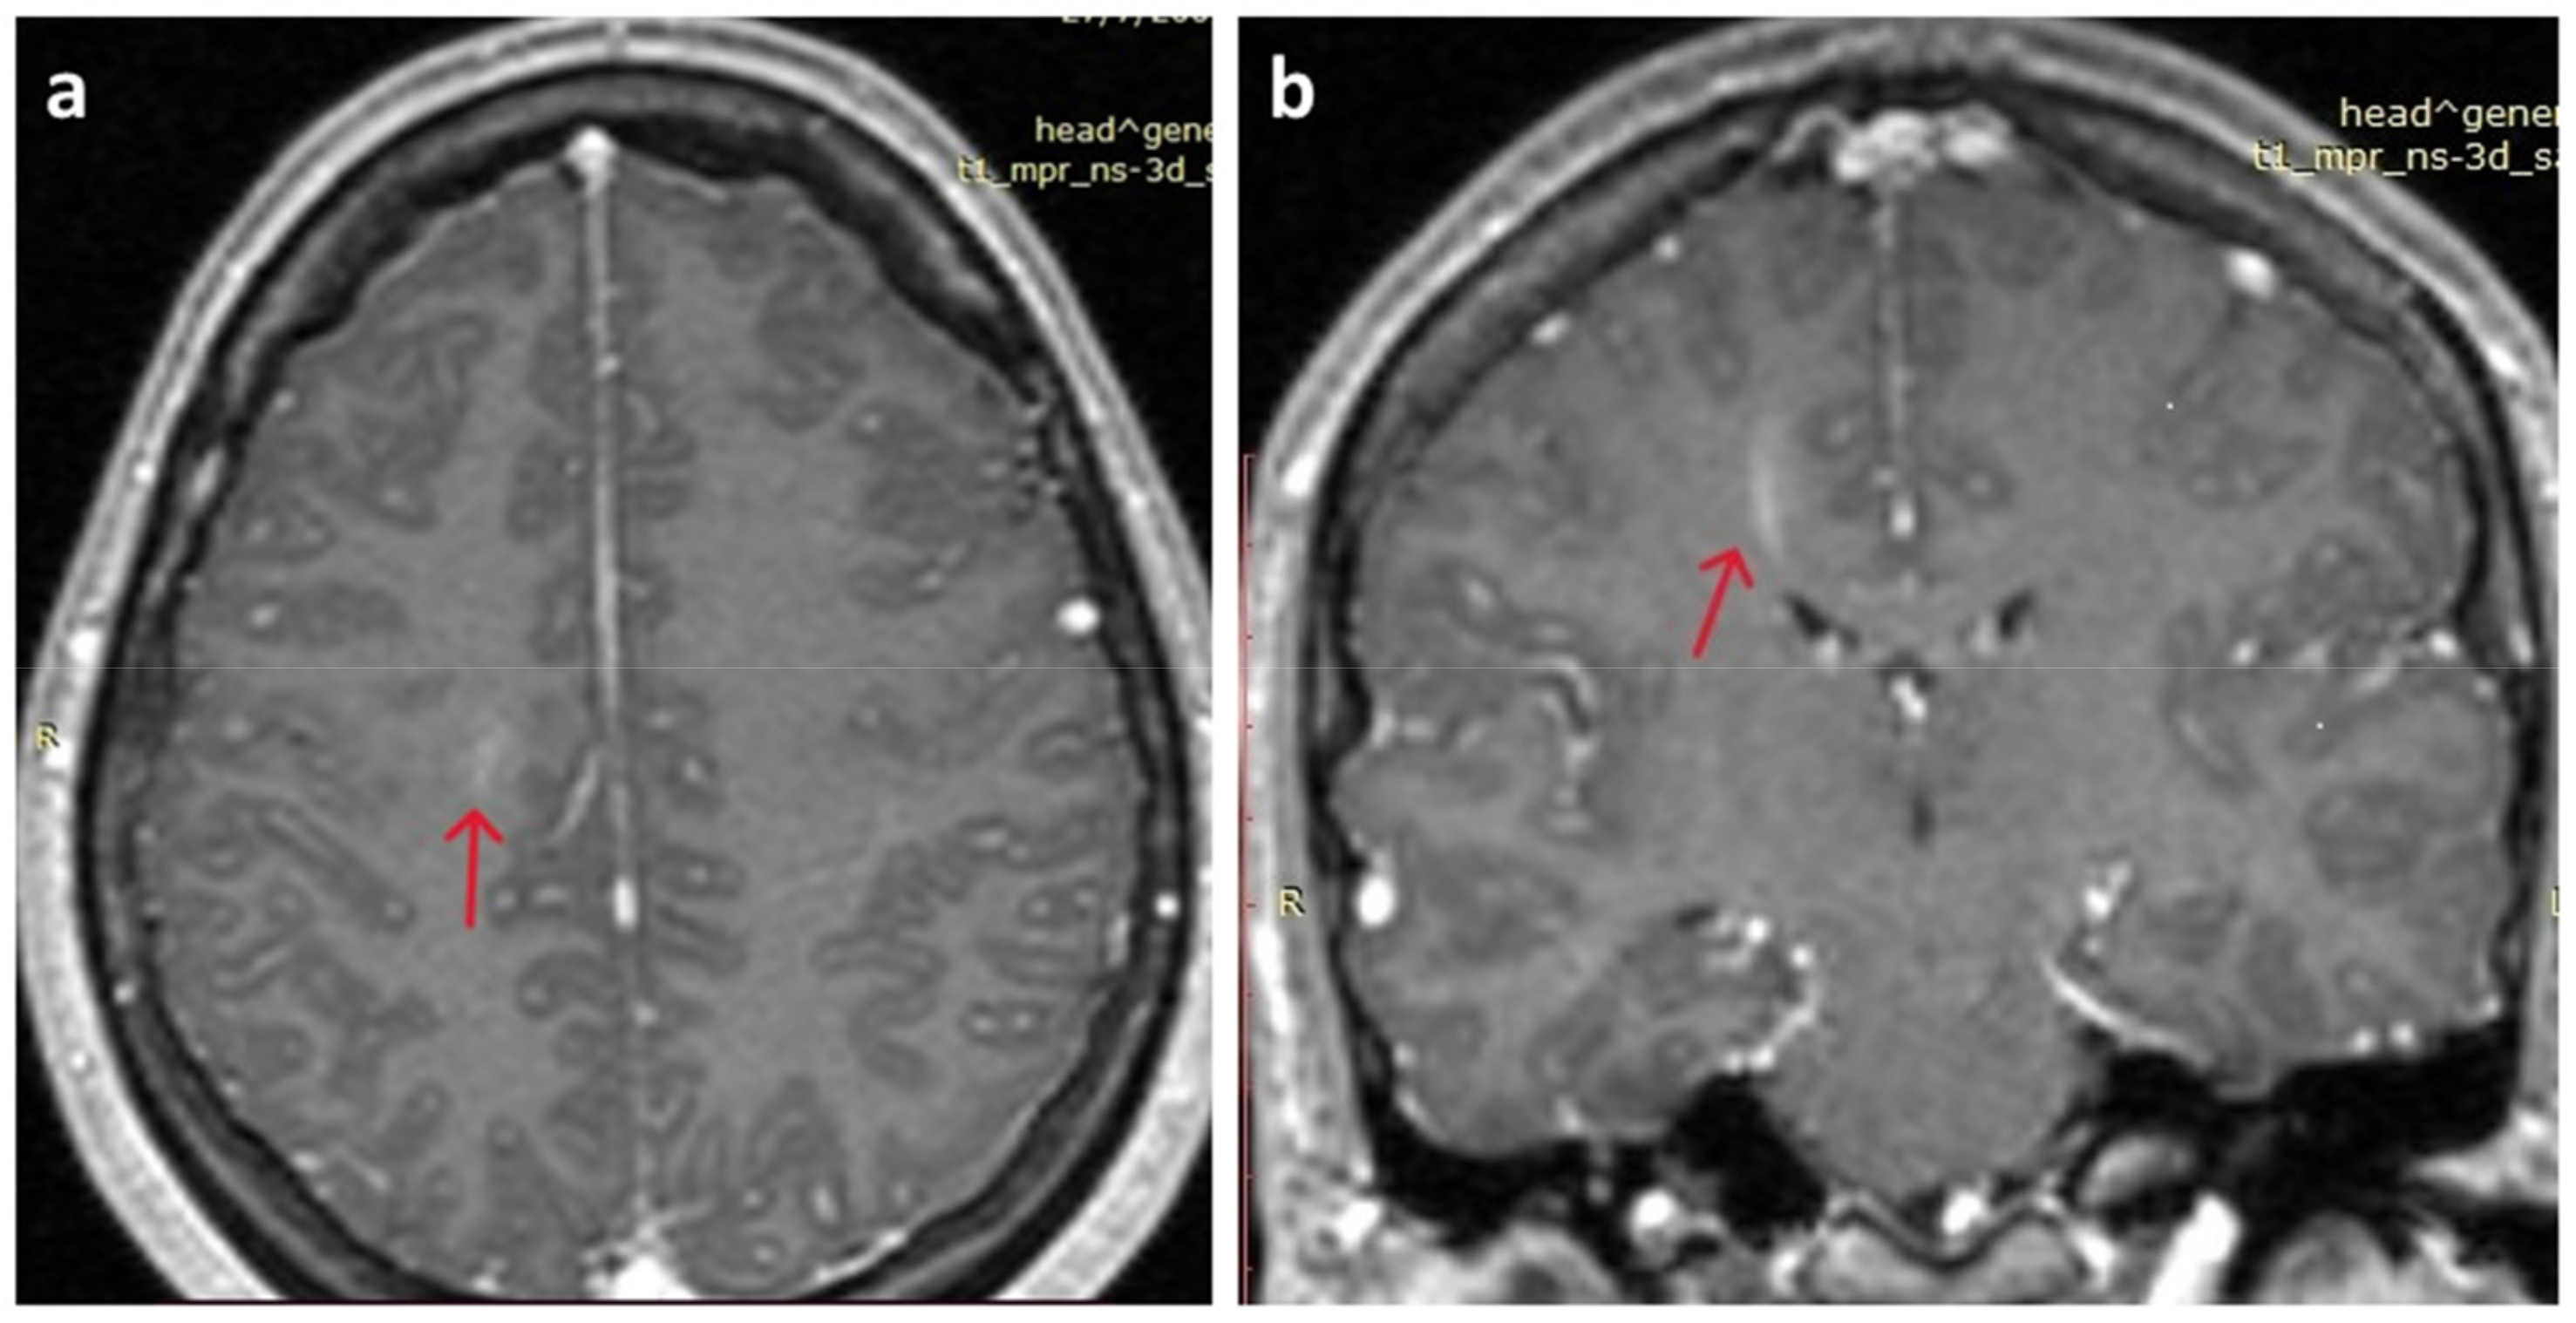

At presentation, neurological assessment did not reveal any focal neurological signs, except for mild meningism with a positive Brudzinski’s sign. Laboratory tests were within the normal limits, as were inflammatory markers. The chest X-ray was unremarkable. A brain CT scan did not reveal any acute pathology. A lumbar puncture was performed, which revealed CSF lymphocytic pleocytosis (350 lymphocytes/μL), mildly elevated protein 69mg/dl (nv < 45 mg/dL), glucose 59mg/dL (within normal limits), and normal LDH, 19mg/dl. Treatment was initiated with IV acyclovir, ceftriaxone, and analgesics. Film array (multiplex PCR) of the CSF did not detect any of the common meningitis/encephalitis pathogens, and CSF did not grow any bacterial or fungal pathogens. Brain MRI was unremarkable, except for leptomeningeal enhancement in both brain and cerebellar hemispheres and a linear enhancing formation in the right centrum semiovale, characterized as a probable venous angioma, which was reviewed by the neurosurgeons and was not considered to be clinically significant (Figure 1). The electroencephalogram (EEG) was within normal limits. Ophthalmological examination (including fundoscopy) was also normal. Muscle relaxant medication (orphenadrine citrate) was added to her treatment, and the antimicrobial/antiviral treatments were discontinued.

Figure 1.

Brain MRI. (a) Mild leptomeningeal enhancement in both brain hemispheres (red arrow); (b) linear enhancing formation in the right centrum semiovale, characterized as a probable venous angioma S (red arrow).